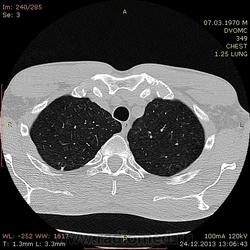

43 года. На флюшке нашли очаг на верхушке. Жалоб нет. Архива нет.

Узелок сязанный с плеврой. Или полость мелкая с толстыми стенками. Наверное, стоит склоняться к туберкулёзу. Хотелось узнать Ваше мнение, коллеги.

Да, действительно, малая полость распада есть. Вероятнее всего, туб этиологии. В настоящий момент, скорее всго, в фазе уплотнения. Желательно обследовать на активность туб. процесса, да оставить на динамическое наблюдение.

Андрей Юрьевич

Посчитала бы за старые очаги, как последствие перенесенного процесса. На фоне парасептальной и центролобулярной эмфиземы в верхушках есть несколько таких очагов, кавитация кажущаяся, из-за близости участка эмфиземы (ИМХО). Рекомендовала бы туб.пробы и КТ-контроль через пару месяцев с записью: на данный момент признаков активности процесса нет.

В саггитале полостюшка смотрится несколько интересно. Создается впечатление буллезной полости с участком уплотненной и частично кальцинированной стенкой. А если исходить из этого, то и дренирующего бронха не будет. Очаги приведенные коллегой ЛГ очень плотные даже на взгляд. Т.е. ТБ если и был, то эта полость не его